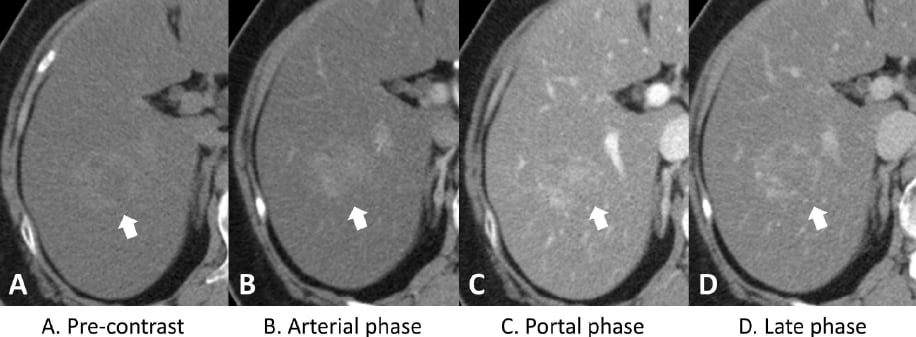

A 3cm ill-defined mass at S6 of liver (arrow) was detected in the background of diffuse hepatic steatosis with decreased attenuation (A). The triple-phase CT scans revealed heterogeneous enhancement of the tumor on the arterial phase (B) and portal phase (C), and without a significant washout on the late phase images(D).

Figure 1. Dynamic computed tomography (CT) of the liver